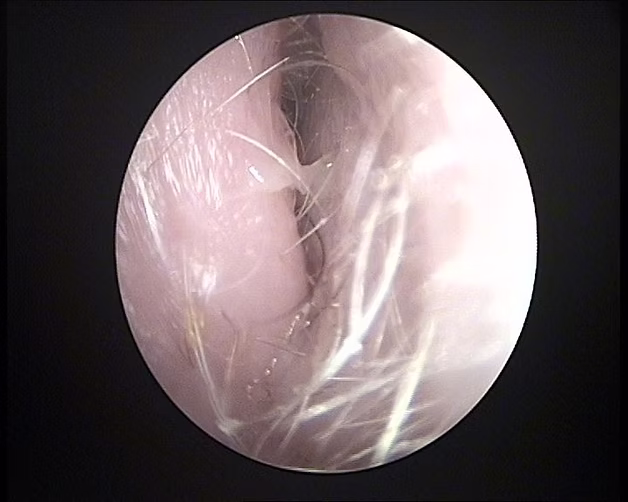

Estenosis conducto auditivo

Se observa piel engrosada y enferma que disminuye el diámetro del conducto. Produce supuración y dolor.